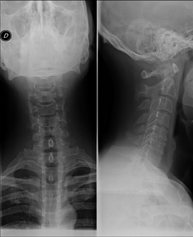

- Cervical spine X-ray

This technique uses X-ray rendered imaging for examining the cervical spine. Indicated for: trauma, cervical pain.

Técnica mediante la cual, utilizando rayos X, se obtienen imágenes del cavum para su estudio. Indicaciones: dificultad respiratoria, anginas de repetición en lactantes y niños. - RX Columna cervical

Técnica mediante la cual, utilizando rayos X, se obtienen imágenes de la columna cervical para su estudio. Indicaciones: traumatismo, contractura cervical, dolor articular. - RX Huesos propios nasales